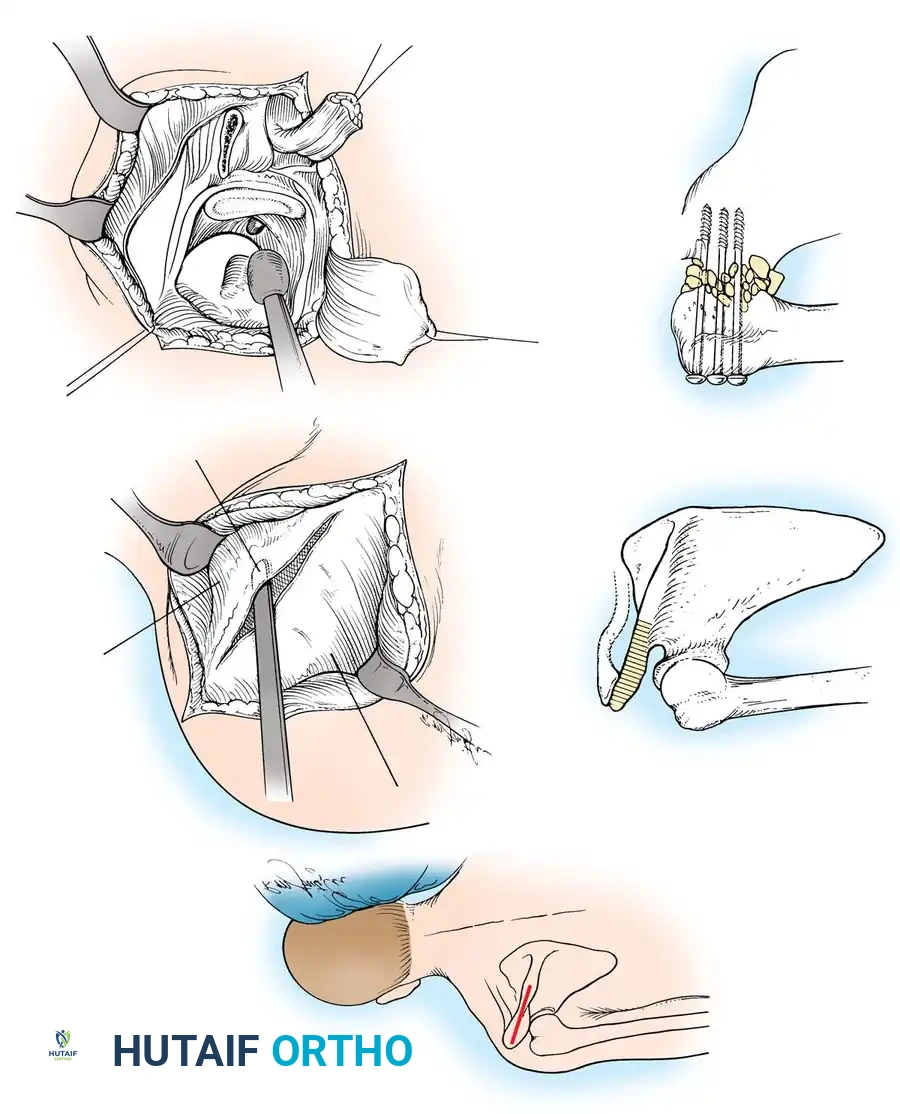

1. Patient Positioning and Incision

The patient is typically placed in a beach-chair position or lateral decubitus position, depending on surgeon preference. The entire forequarter, including the neck, chest, and arm down to the hand, must be prepped and draped free to allow for intraoperative assessment of arm positioning.

A broad strap incision is utilized. The incision begins over the spine of the scapula, extends laterally over the acromion, and curves distally down the anterolateral aspect of the humerus.

2. Surgical Exposure

The deltoid muscle is split or reflected off the anterior and lateral acromion. The underlying rotator cuff tendons (supraspinatus, infraspinatus, and subscapularis) are systematically excised to fully expose the articular surfaces of the humeral head and the glenoid fossa. The undersurface of the acromion is also exposed, as it will serve as a secondary fusion bed.

3. Joint Preparation and Decortication

Meticulous preparation of the bony surfaces is paramount to achieving a solid arthrodesis. All articular cartilage must be aggressively removed using a combination of osteotomes, gouges, and high-speed burrs.

The glenoid is decorticated down to bleeding subchondral bone. The humeral head is similarly denuded. To maximize the surface area for fusion, the undersurface of the acromion is decorticated, and a corresponding flat surface is created on the superior aspect of the greater tuberosity.

In some techniques, an intra-articular osteotomy of the humeral head is performed to create a flat, broad cancellous surface that perfectly mates with the decorticated glenoid.

4. Provisional Fixation and Positioning

The arm is placed into the predetermined optimal position (20-30° abduction, 20-30° flexion, 40° internal rotation). The hand-to-mouth test is performed. Once the position is confirmed, heavy Steinmann pins or K-wires are driven from the lateral humerus, through the humeral head, and into the glenoid vault to provisionally hold the construct.

5. Rigid Internal Fixation

The most robust biomechanical construct involves a heavy, malleable plate (such as a 10- to 14-hole 4.5mm pelvic reconstruction plate or a dynamic compression plate). The plate is meticulously contoured to lie flat along the spine of the scapula, bend over the acromion, and extend down the lateral shaft of the humerus.

Screws are placed sequentially:

1. Scapular Spine: Cortical screws are placed into the dense bone of the scapular spine.

2. Acromiohumeral Fixation: Screws are passed through the plate, across the acromion, and into the humeral head.

3. Glenohumeral Fixation: Long, fully threaded cortical or cancellous screws are directed through the plate, through the humeral head, and deep into the glenoid neck and vault. This is the most critical step for achieving compression across the primary fusion site.

4. Humeral Shaft: The distal portion of the plate is secured to the humeral diaphysis.

If additional stability is required, or if bone quality is poor, a second plate (double plating technique) can be applied posteriorly.

Radiographic confirmation of a contoured reconstruction plate achieving rigid acromiohumeral and glenohumeral compression.

Alternative Fixation: Screw-Only Constructs

In cases where soft-tissue coverage is extremely poor, or hardware prominence is a major concern, a screw-only construct may be utilized. This involves passing multiple large-fragment (6.5mm or 7.3mm) cannulated screws from the proximal humerus into the glenoid, and from the acromion into the humeral head. While this requires less dissection, it is biomechanically inferior to plate fixation and often necessitates postoperative spica casting.

6. Bone Grafting

Autogenous bone graft is highly recommended to augment the fusion mass. Local bone resected from the humeral head or acromion can be packed into the interstices of the fusion site. If local bone is insufficient or of poor quality (e.g., in cases of infection or failed arthroplasty), autologous iliac crest bone graft (ICBG) should be harvested and packed around the glenohumeral and acromiohumeral interfaces.